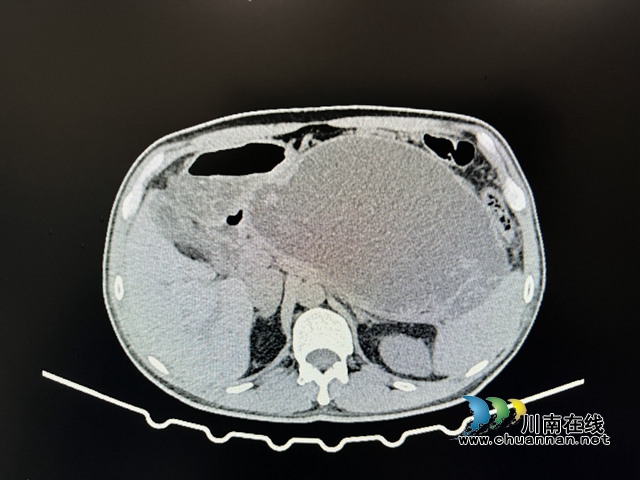

近日,西南医科大学附属中医医院呼吸内科支气管镜下异物取出术、支气管镜下冷冻治疗(-70℃~-80℃),成功为一位支气管异物、支气管肉芽肿的患者取出支气管异物,从而改善了气道狭窄,缓解了临床症状。近一年来,59岁的艾大叔反复出现咳嗽、咯白色粘...